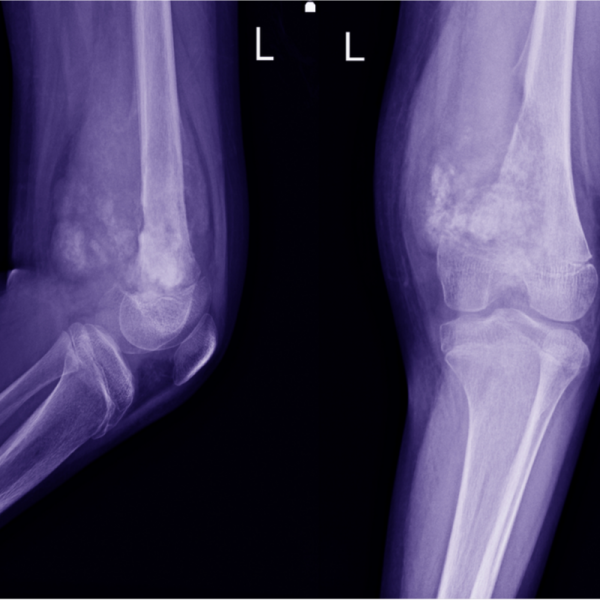

Osteosarkoma

Jvinga sarkoma

Kaulu vēzis